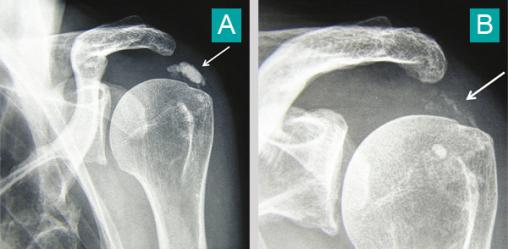

© Pascal Guggenbuhl (La Revue du Praticien)

Tendinopathie calcifiante de l'épaule (A). Noter sa quasi disparition après une crise douloureuse aiguë hyperalgique (B). Voir : Guggenbuhl P, Coiffier G, Albert JD, Chalès G. Dossier. Arthropathies microcristallines. Rev Prat 2015;65(5):665-82.